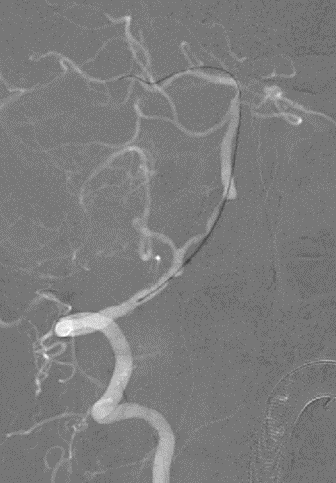

左椎动脉+左颈动脉造影:

导丝怎么扩【载药时代 球扩天下】NOVA DES®颅内药物洗脱支架在椎动脉颅内段重度狭窄的应用二例_https://www.jmylbn.com_新闻资讯_第21张

导丝怎么扩【载药时代 球扩天下】NOVA DES®颅内药物洗脱支架在椎动脉颅内段重度狭窄的应用二例_https://www.jmylbn.com_新闻资讯_第22张

导丝怎么扩【载药时代 球扩天下】NOVA DES®颅内药物洗脱支架在椎动脉颅内段重度狭窄的应用二例_https://www.jmylbn.com_新闻资讯_第23张

病变情况分析:右桡动脉穿刺,置6F桡动脉鞘管,5F多功能导管在泥鳅导丝辅助下脑血管造影提示:右椎动脉V4段重度狭窄(约90%)。

泥鳅导丝携5F 115cm颅内支撑导管,至右椎动脉V2段。

在颅内支撑导管支撑下,将0.014'' 300cm微导丝,通过狭窄节段将其放置在基底动脉中段。将2.0mm*10mm球囊打起预扩狭窄部位,然后更换赛诺神畅 颅内药物洗脱支架NOVA DES® 2.5*10mm延微导丝顺利通过狭窄节段,再次造影见定位准确,缓慢扩张球囊释放支架。